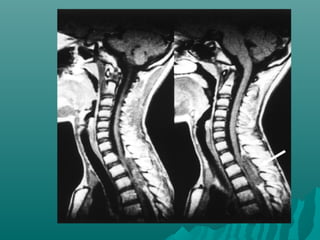

 Resonancia magnética de la columnaResonancia magnética de la columna

Diferencia de protrusión discalDiferencia de protrusión discal

VisualizaVisualiza toda la columnatoda la columna en un soloen un solo

examenexamen

Identifica compresión posterior,Identifica compresión posterior,

anterior,anterior,

y masas paraespinales - posterolat.y masas paraespinales - posterolat.

Identifica compromiso meníngeo -Identifica compromiso meníngeo -

con Cte.con Cte.

Excelente para mets. IntramedularesExcelente para mets. Intramedulares

Más sensible (93%) y específicaMás sensible (93%) y específica

(97%)(97%)

Discrimina mejor entre Benigno yDiscrimina mejor entre Benigno y

MalignoMaligno

Evita ulteriores estudios - AhorraEvita ulteriores estudios - Ahorra

tiempo y $tiempo y $

Orienta tratamiento radianteOrienta tratamiento radiante

TOMOGRAFIA COLUMNATOMOGRAFIA COLUMNA

 Evalúa mejor la destrucción óseaEvalúa mejor la destrucción ósea

Y destrucción vertebral.Y destrucción vertebral.

Util en planificación quirúrgicaUtil en planificación quirúrgica

Pero...Pero...

No distingue bien laNo distingue bien la

médula espinalmédula espinal

Pobre evaluación del sacoPobre evaluación del saco

tecaltecal

Ej: próstata y mielomaEj: próstata y mieloma